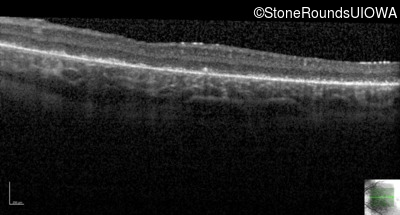

Age at visit: 8 years

OD OS

This 8 year old girl had normal vision until age 6 when she failed a school vision screening. That year, she was able to play softball well, but this year she often loses sight of the ball and is often hit by it.